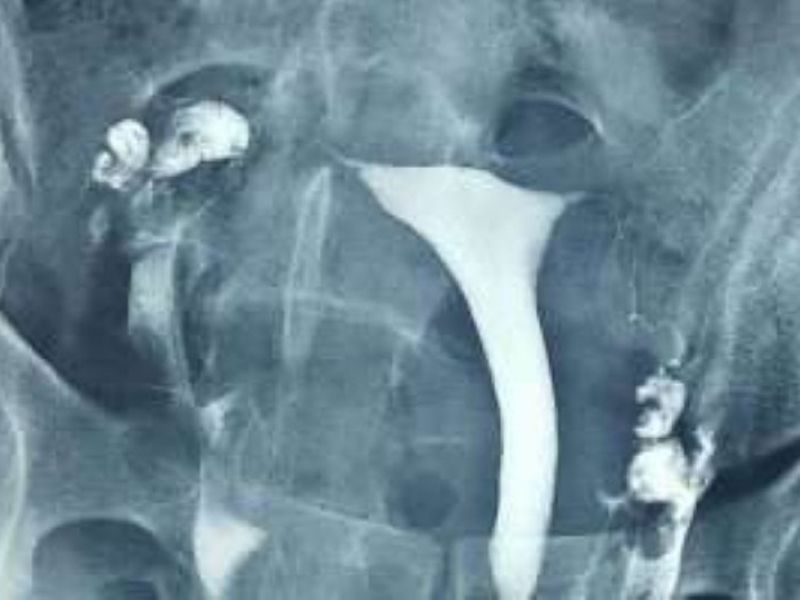

Myom

Rahim sağındaki iri myom kitlesi rahim boşluğu alt kısmının uzamasına ve sola doğru itilmesine sebep olmuş.